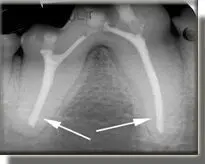

Patient with a fractured lower first molar and exposure of the pulp (nerve) chamber.